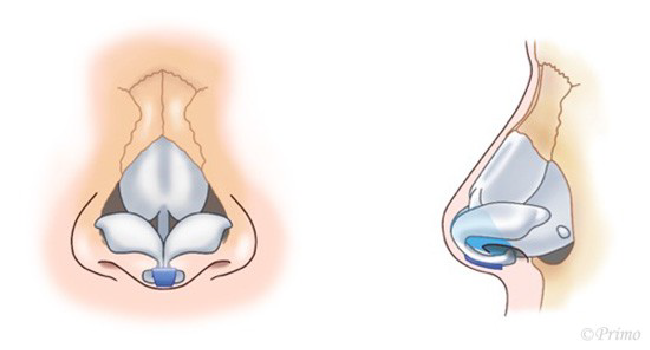

鼻の美しさの基準として鼻翼-鼻柱関係ACR(alar-columellar relationship)という指標があります。

ACRとは左右の小鼻の付け根を結んだ線を底辺、鼻柱を頂点としてできる三角形の位置関係のことで、この形が下向きの二等辺三角形であることが理想的とされています。

反対に鼻柱基部が鼻翼基部より頭側に位置する状態は、鼻柱後退(retracted columella)と呼ばれ、美容的に良好な形態とは言えません。

鼻中隔延長術により鼻柱をしっかりと降ろすことで小鼻の位置が相対的に上がり、ACRを改善させることができます。

小鼻の位置や形態を整える施術は他にも複数あり、患者様の鼻の状態、ご希望にあわせて適切な施術方法を選択することで、自然な仕上がりを実現いたします。

青い部分が移植した軟骨です。この軟骨の固定により、鼻の高さ、細さ、向きが大きく調節できます。